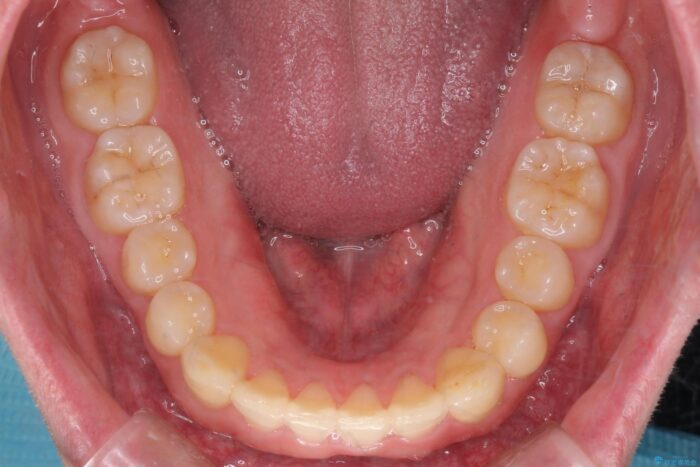

下の歯のがたつきが気になるとご来院されました。

歯のがたつきが改善され大変お喜びいただけました。